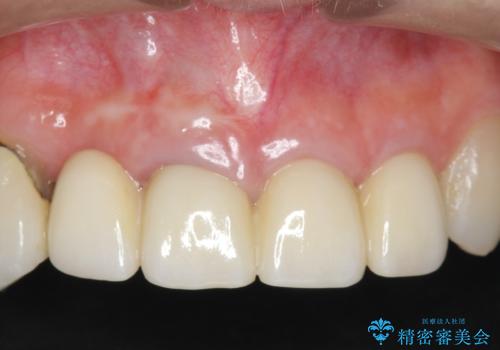

噛み合わせが深く、前歯の突き上げが大きいため欠けの繰り返しを防ぐべくセラミッククラウンによる補綴を行うこととしました。

審美性の改善を達成することができました。